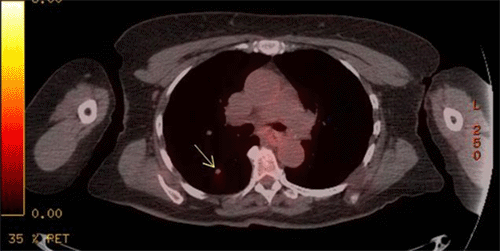

The core needle biopsy slides from the outside facility were submitted for second and third opinions to our institution's pathology department and Memorial Sloan Kettering, which confirmed metastatic sarcoma. She then underwent a bilateral breast magnetic resonance imaging (MRI) (Figure 1) as well as a whole-body positron emission tomography (PET) scan. PET scan showed mild uptake (1.5 standard uptake value [SUV]) of a 9 mm nodule in the right lower lobe of the lung (Figure 2) as well as in the right breast mass. After a multidisciplinary tumor board discussion, it was decided that surgical excision of the breast mass with a sentinel lymph node biopsy would precede chemotherapy. While there is little evidence for lymph node metastasis in liposarcoma, a sentinel node biopsy was performed for a more thorough approach to the breast lesion. The medical oncology team agreed this would be an appropriate course, given that her sub-centimeter pulmonary nodule did not necessarily mandate systemic treatment in the neoadjuvant setting. Moreover, the patient herself was very motivated to have her mass removed as it was causing her pain and discomfort.

Figure 1. Bilateral breast MRI with intravenous (IV) contrast Axial T2 STIR sequence. Published with Permission

Image depicts right breast mass with intimal connection with pectoralis muscle, 3 x 3.5 x 4.5 cm, very dense lobulated mass with postbiopsy clip marker

Figure 2. Bilateral breast MRI with intravenous (IV) contrast Sagittal T2 STIR sequence. Published with Permission

Image depicts right breast mass with intimal connection with pectoralis muscle, 3.0 × 3.5 × 4.5 cm, very dense lobulated mass with postbiopsy clip marker